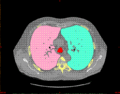

- Image import from CT (DICOM)

- Image segmentation

Materialise Mimics calculates surface 3D models from stacked image data such as Computed Tomography (CT), Micro CT, Magnetic Resonance Imaging (MRI), Confocal Microscopy, X-ray and Ultrasound, through image segmentation. The ROI, selected in the segmentation process is converted to a 3D surface model using an adapted marching cubes algorithm that takes the partial volume effect into account, leading to very accurate 3D models.[2][3] The 3D files are represented in the STL format.